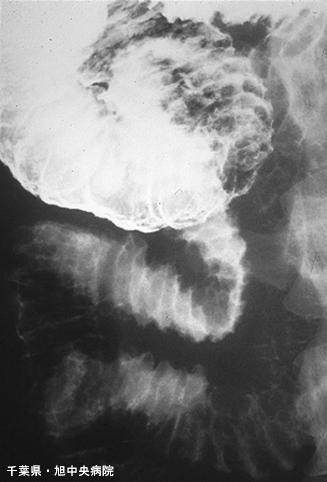

症例提示(所在地,施設名等): 旭中央病院 (Dr. 吉田,村越)

疾患(病理主体)の分類炎症性・潰瘍性疾患/消化管アミロイドーシス

部位(臓器別)小腸/2つ以上

検査方法X-P